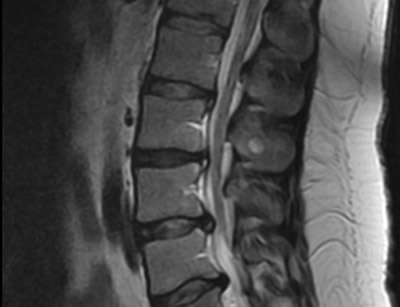

GALLERY

Images gallery